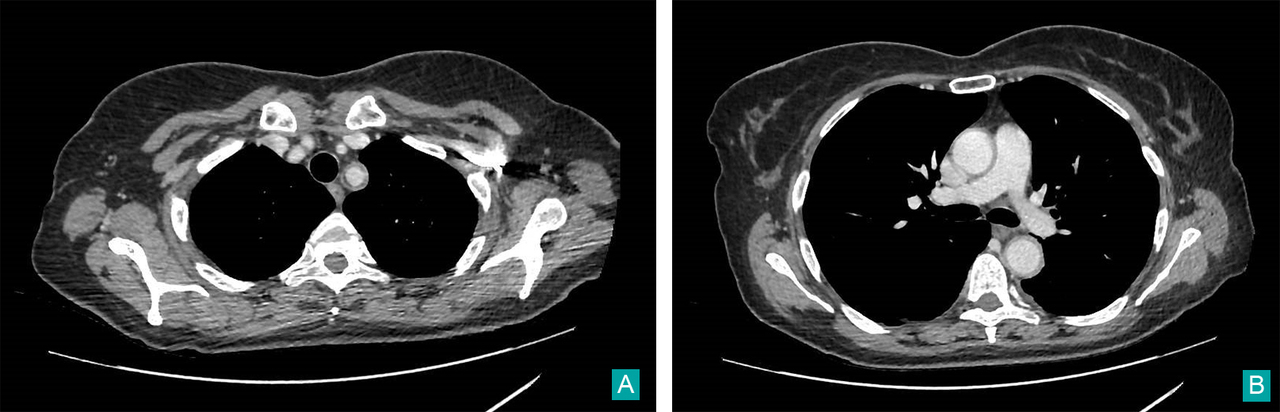

Il s’agit de céphalées matinales d’évolution progressive depuis un mois devant faire évoquer une hypertension intracrânienne et toutes ses causes (y compris une thrombose veineuse cérébrale), une méningite chronique, une hypertension artérielle incontrôlée, ou une artérite a cellules géantes.